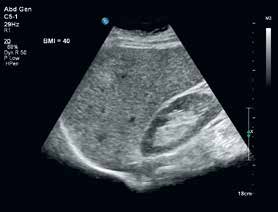

PureWave纯净波技术为成像困难患者的广泛应用提供了全新的解决方案,例如支持困难腹部和胎心成像患者的PureWaveC5-1探头。(来源:成贯仪器)

增强的PureWave技术显示卓越的腹部及胎心图像品质。